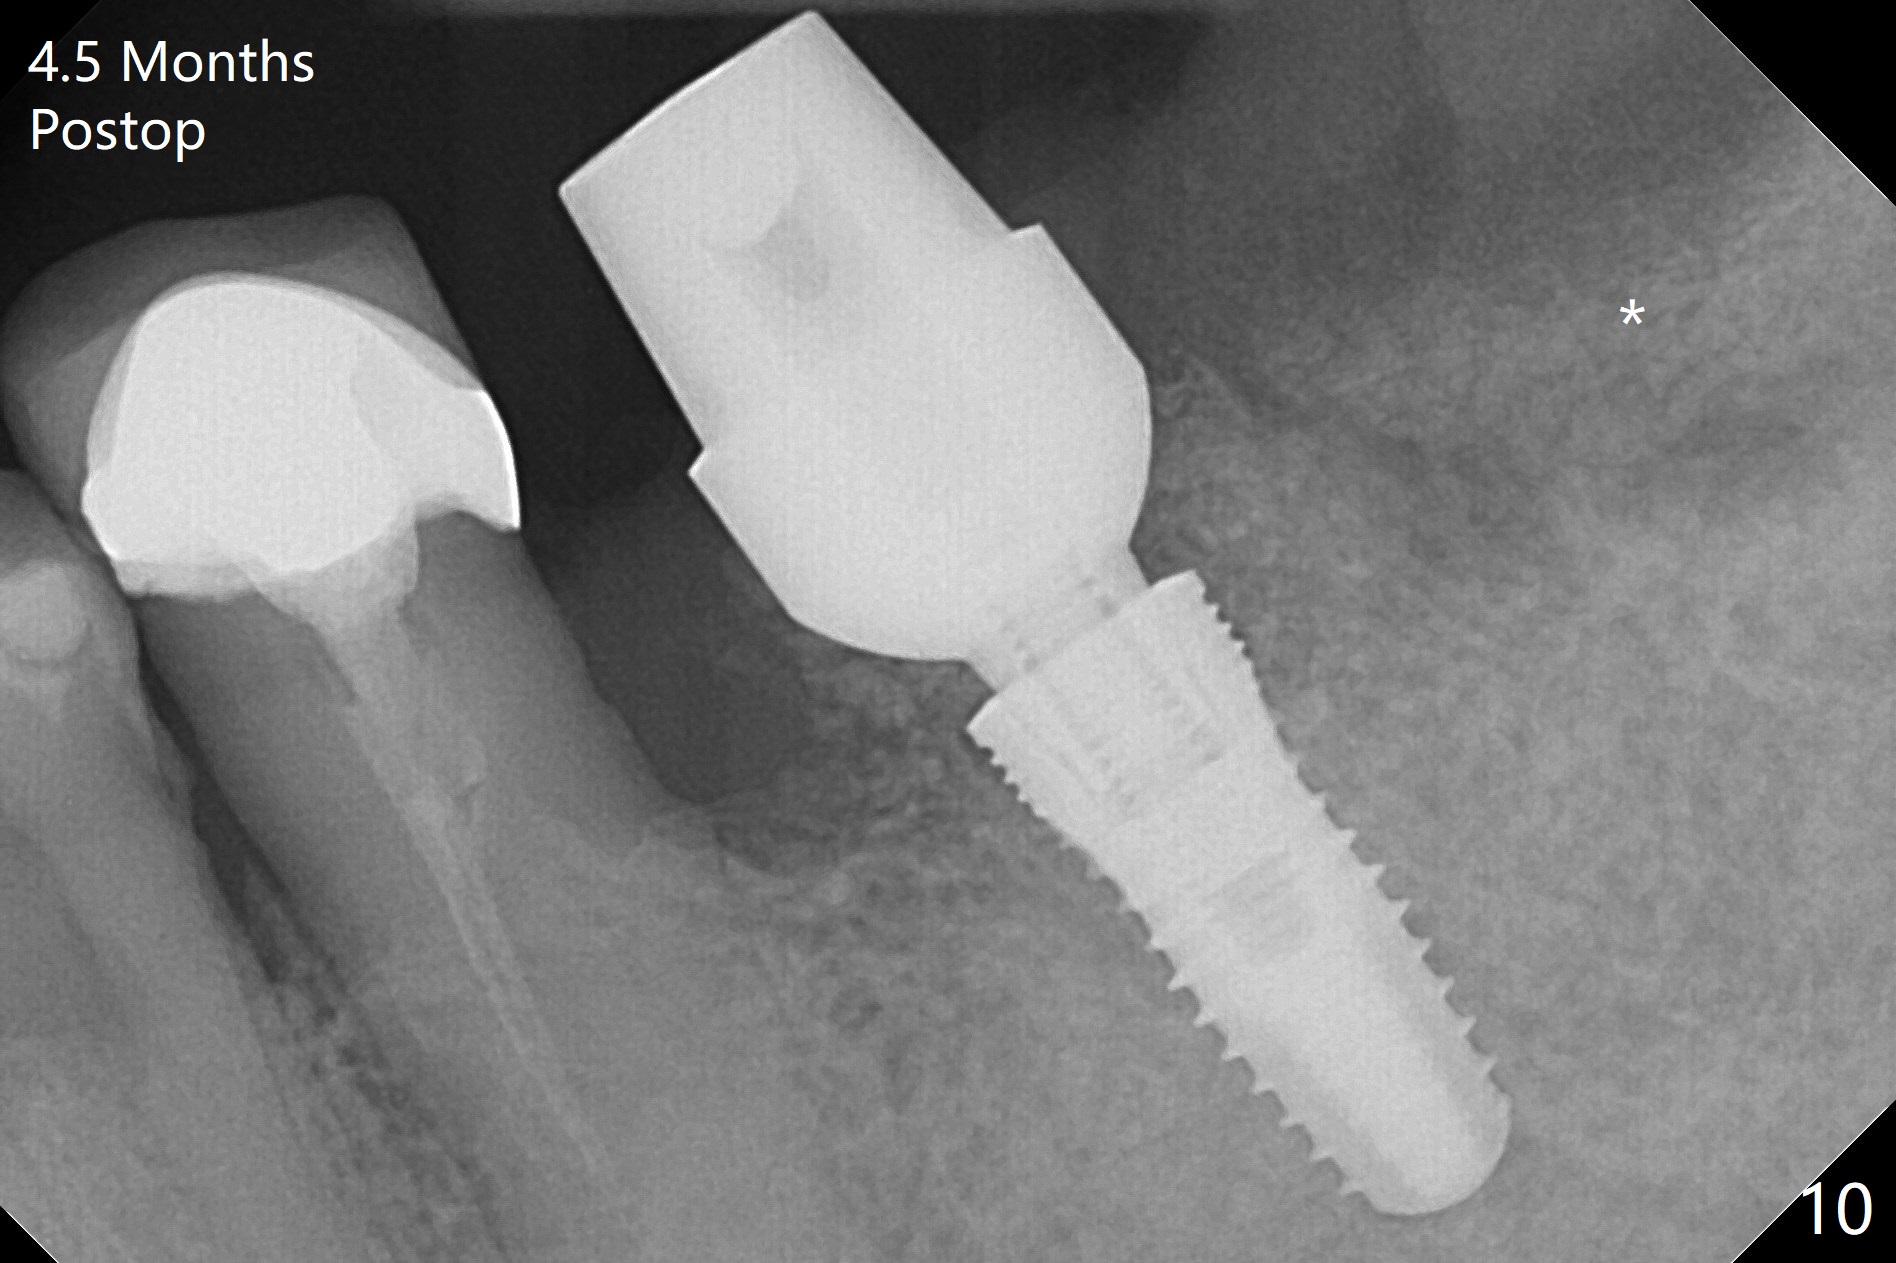

After extraction of the supraerupted tooth #19 with severe buccal gingival recession, the buccal and lingual plate are found to be lost. The sockets are fused and flat without the septum. The bone is hard and painful for the initial osteotomy with infiltration anesthesia (Fig.2). Following block anesthesia, the initial osteotomy depth extends to 8 mm (Fig.3,4). With apparent 4.9 mm clearance, the osteotomy is further extended to 10 mm. The osteotomy walls are apparently intact without severe hemorrhage after each drill. Due to the thick gingiva and severe bone loss, a 5x12 mm implant is intentionally placed 3 mm above the base of the socket bone (Fig.5,6 (yellow dashed line)). Vanilla Cortical and Cancellous allograft (Fig.6 *) is placed around the exposed implant and 7.8x5(6) mm abutment with 4 and 2 mm buccal and lingual gaps. Next collagen plug cut in strip is placed to fill the most coronal aspect of the socket (Fig.7 *). The buccal and lingual gingivae are approximated with sutures proximally. Finally periodontal dressing is applied. Since the Inferior Alveolar Canal is vague in intraop PAs (Fig.4,5), there is worry about potential nerve damage during and after osteotomy. This should be no issue if preop panoramic X-ray is reviewed with measurement (Fig.8). The bone graft appears to remain in place nearly 4 months postop (Fig.9). Two weeks later, he returns for impression. When the provisional is removed, the gingiva is unhealthy. Without the provisional and with improved oral hygiene, the gingiva is healthy one week later, but the tooth #18 is symptomatic. The latter is extracted with socket preservation (Fig.10 *). There is no apparent bone loss around the implant at #19 6.5 months post cementation (Fig.11).